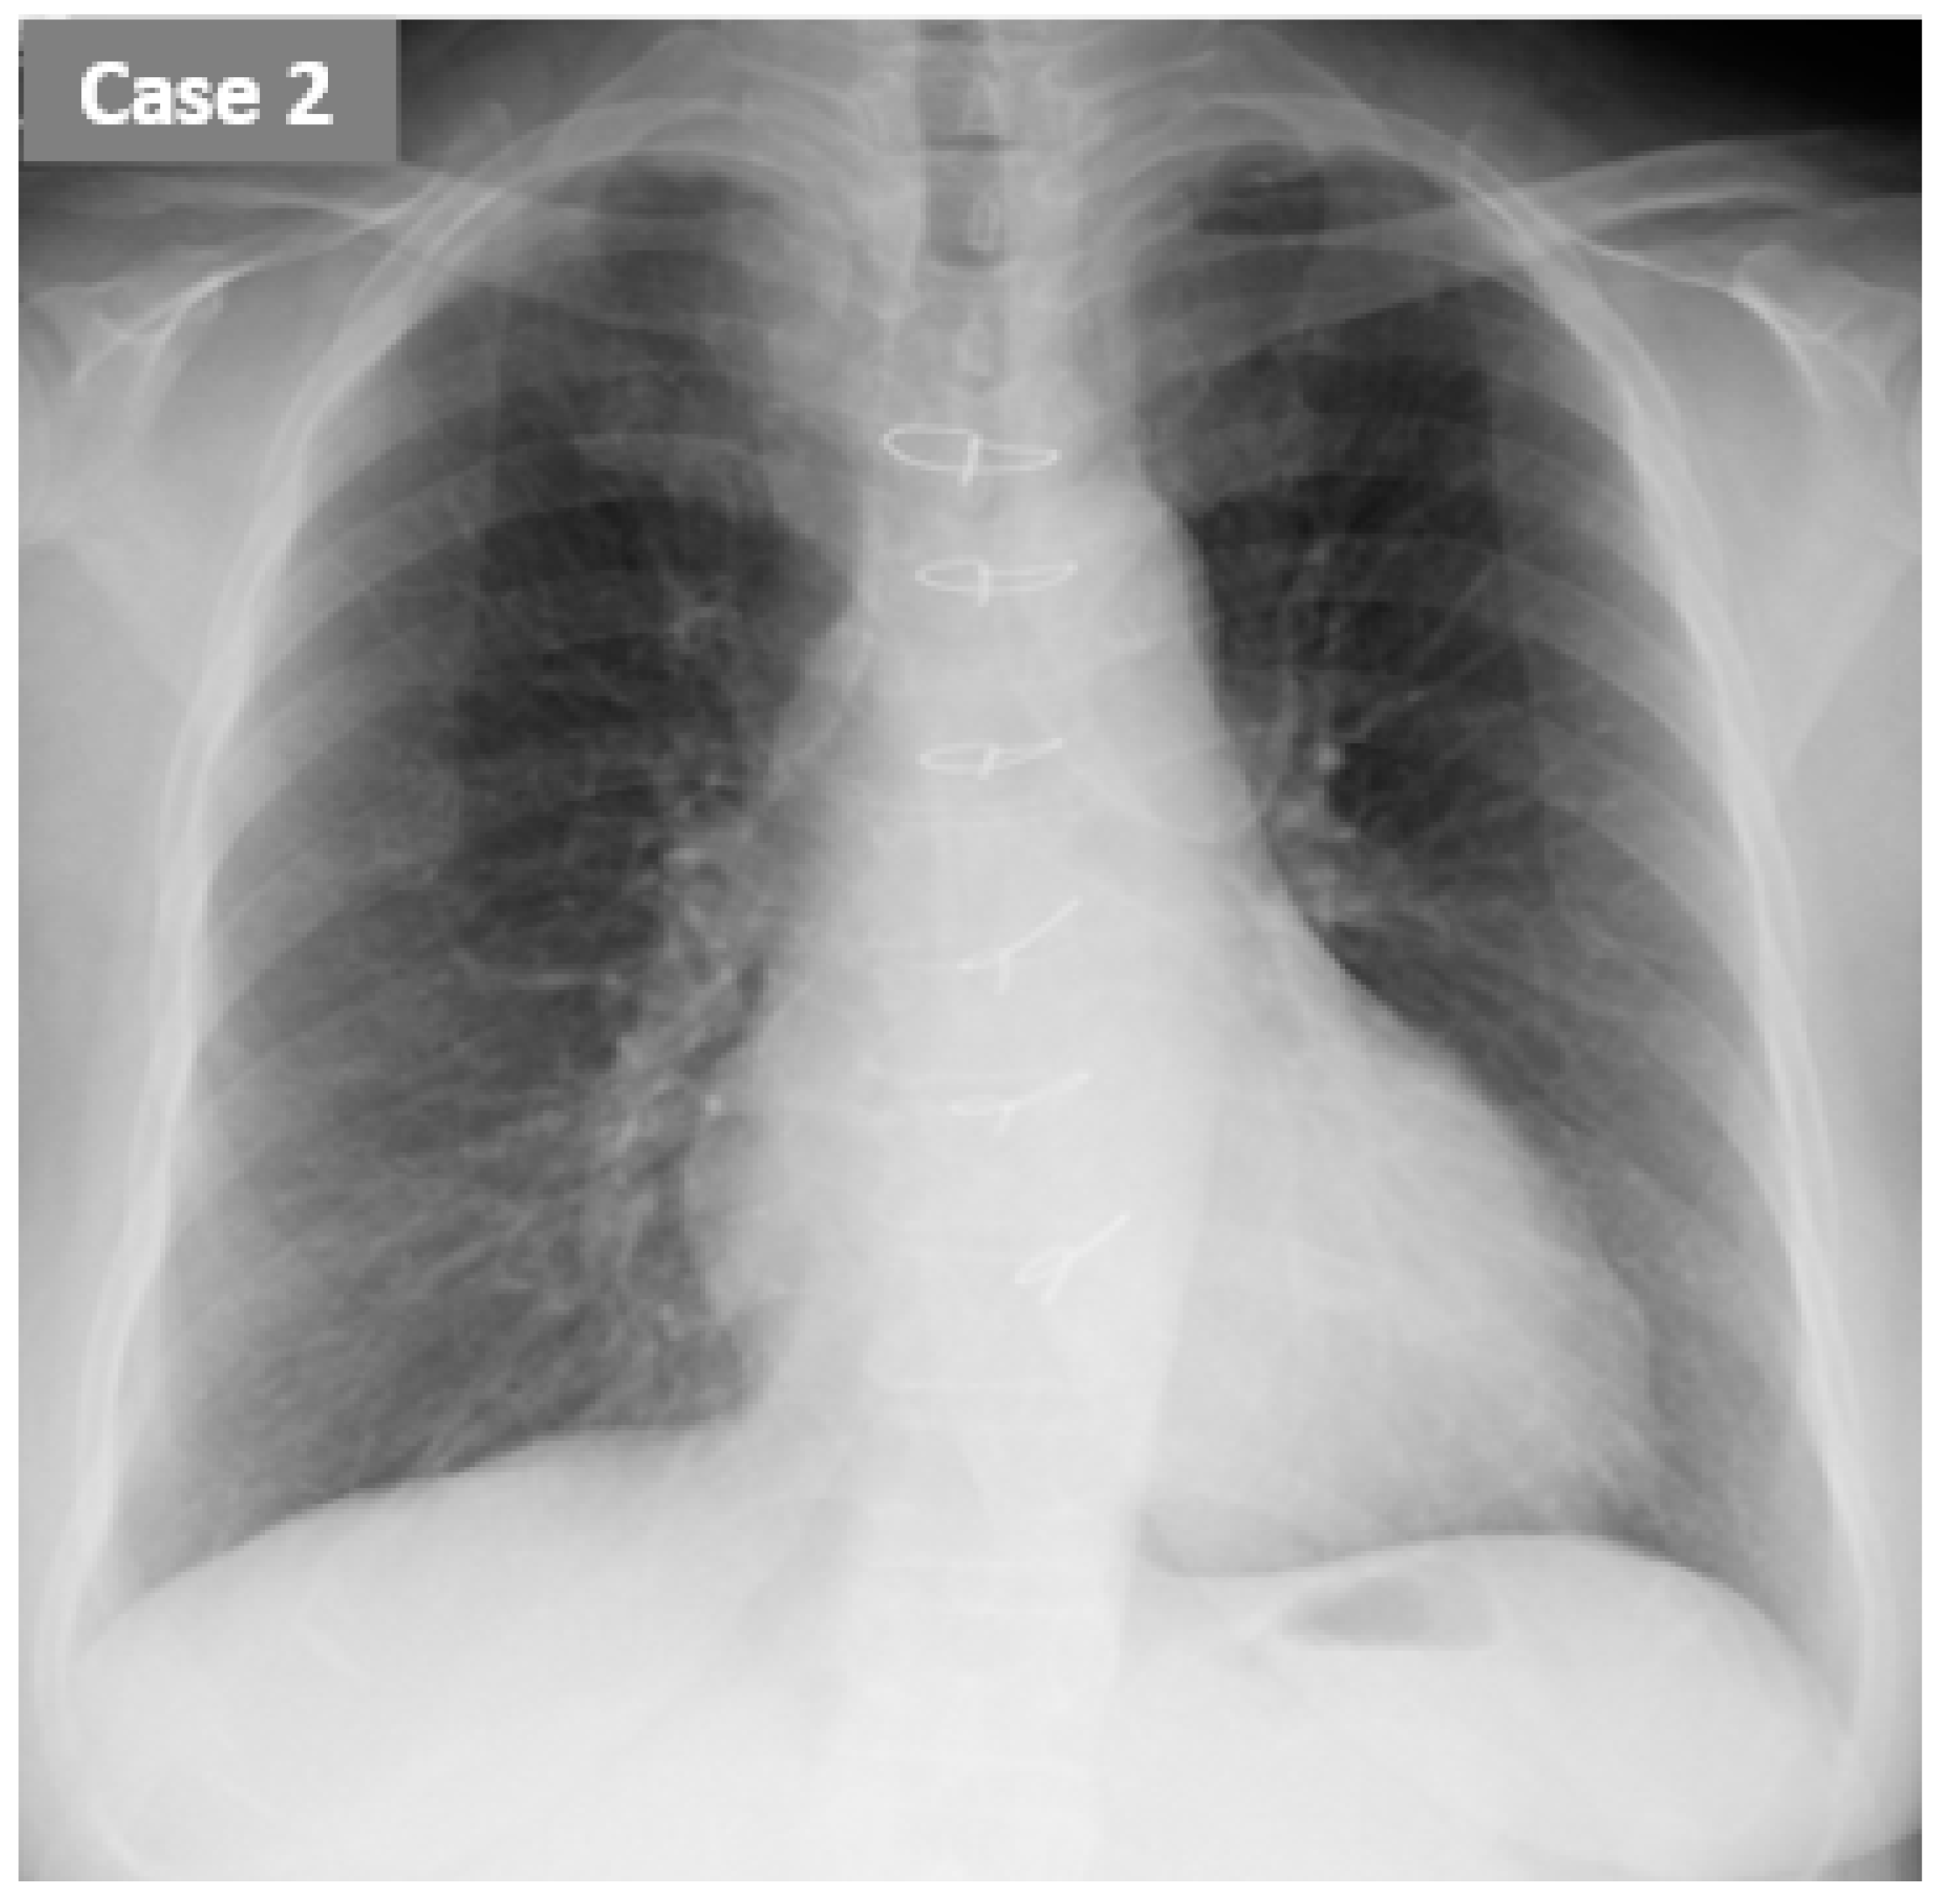

2.2. CASE 2 (ReDS Change from 37 to 27%)